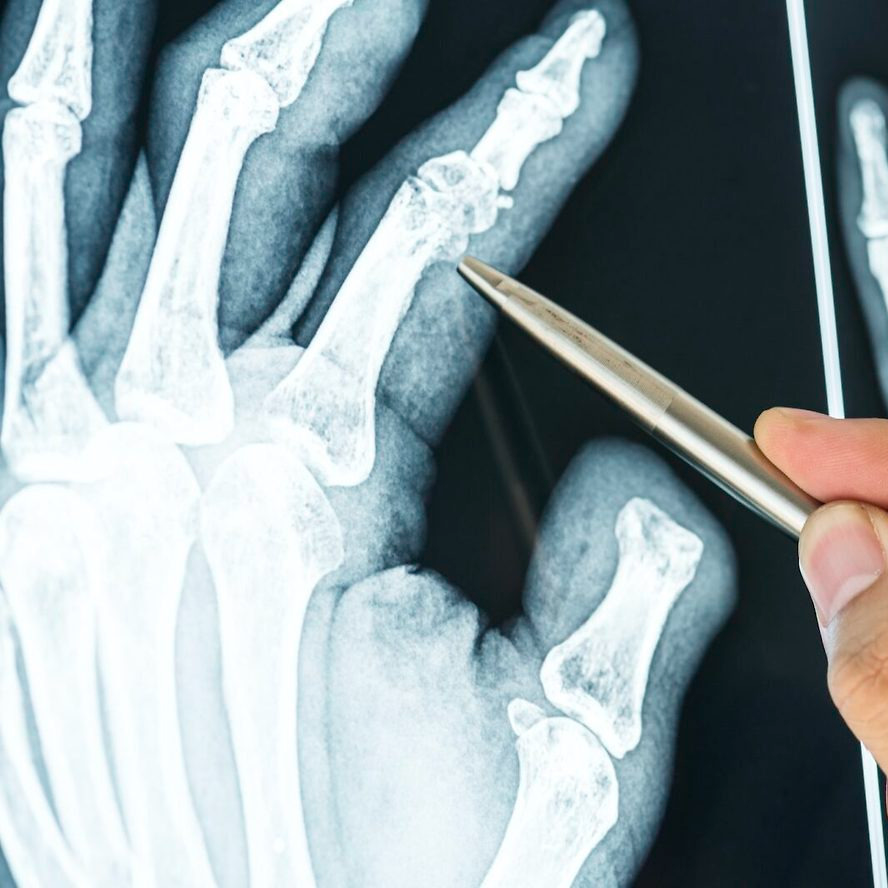

손가락 골절은 기저부(base) 골절, 중간부(shaft) 골절, 관절면(intra-articular) 골절 등으로 나뉘며, 특히 관절면을 침범한 골절은 기능적 후유증이 남을 위험이 높습니다. 따라서 엑스레이 검사로 정확한 위치와 손상 정도를 파악하고, 필요 시 CT나 초음파로 인대 손상 여부를 함께 확인해야 합니다.

손가락에 금이 갔을 때 중요한 것은 정확한 진단입니다. 단순히 통증이 있다고 해서 자가진단으로 테이핑만 하는 것은 위험하며, 반드시 엑스레이 검사를 통해 뼈의 정렬 상태와 골절선을 확인해야 합니다.